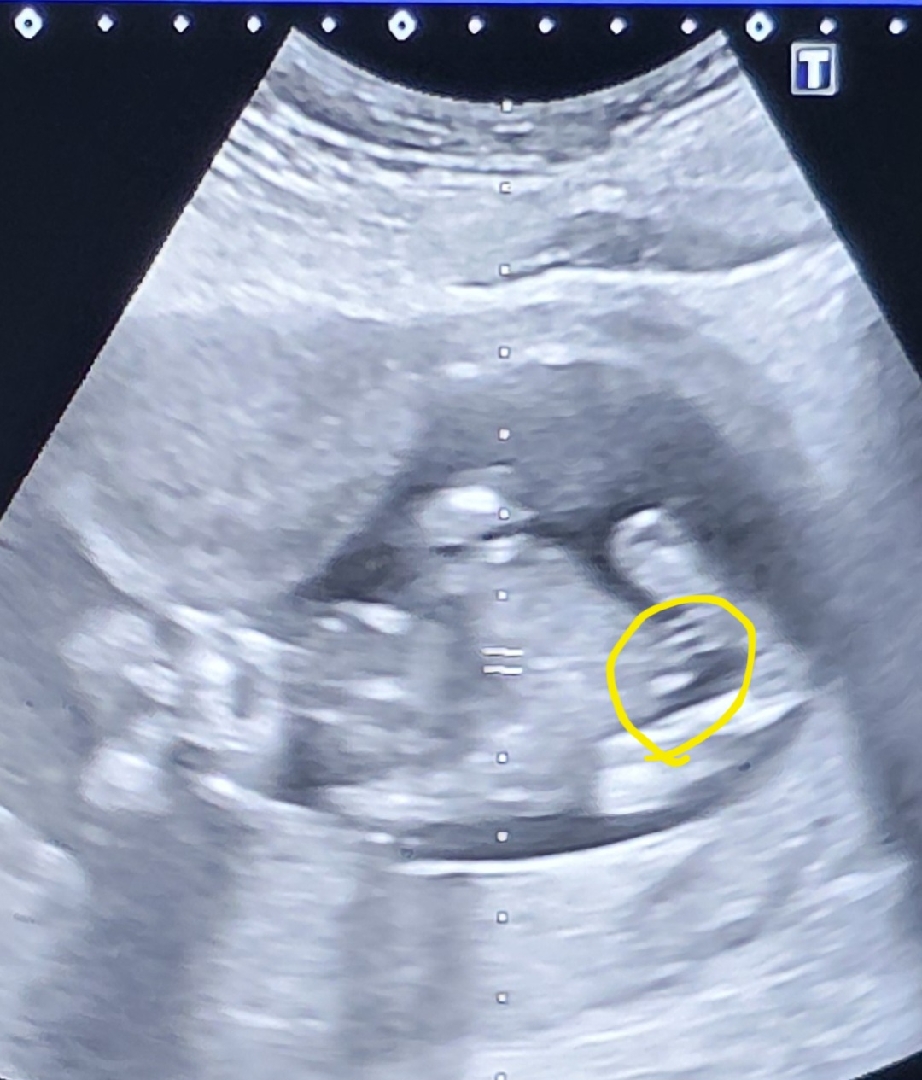

15주 5일 촘파 봐주세용 ..

아기가 정면으로 아빠다리 ? 하고있는 자센데 저번주엔 95% 딸같다하셨거든여 ... 오늘 병원 갈일잇어서 갔는데 혹시 저거 🌶 츄 ..인가여 ?